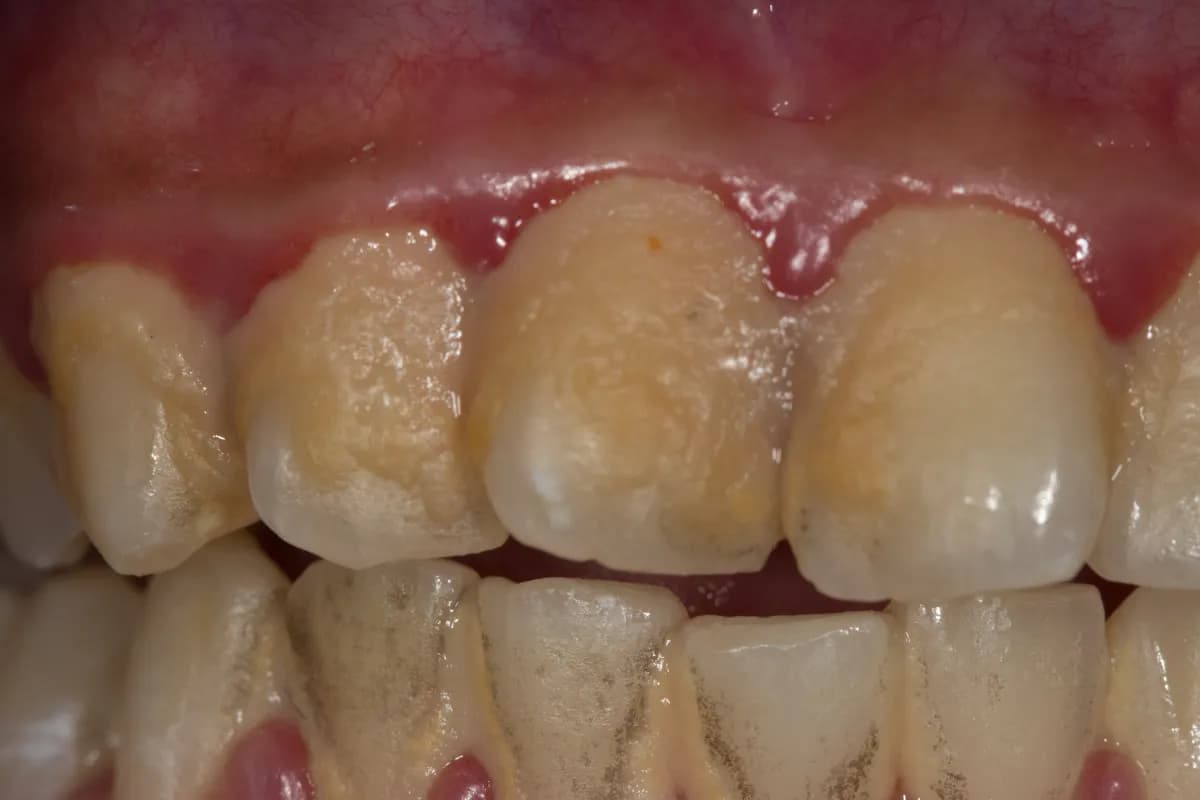

Nagromadzenie kamienia nazębnego może prowadzić do poważnych problemów zdrowotnych oraz estetycznych. Główne zagrożenia związane z kamieniem to choroby dziąseł i próchnica zębów. Kamień nazębny tworzy twardą warstwę, która utrudnia prawidłowe szczotkowanie zębów, co sprzyja rozwojowi bakterii. Te bakterie mogą prowadzić do zapalenia dziąseł, które objawia się ich zaczerwienieniem, obrzękiem oraz krwawieniem. Jeśli nie zostanie to w porę leczone, może dojść do poważniejszych schorzeń, takich jak parodontoza, która zagraża utracie zębów.

Kamień nazębny jest główną przyczyną wielu problemów zdrowotnych w jamie ustnej. W pierwszej kolejności, może prowadzić do zapalenia dziąseł, które jest stanem zapalnym tkanek otaczających zęby. Objawy obejmują ból, obrzęk i krwawienie podczas szczotkowania. Jeśli zapalenie nie zostanie wyleczone, może przerodzić się w poważniejsze schorzenie, takie jak parodontoza, która może prowadzić do utraty zębów. Dodatkowo, kamień nazębny sprzyja powstawaniu próchnicy, ponieważ bakterie w płytce nazębnej produkują kwasy, które niszczą szkliwo zębów. To wszystko sprawia, że regularne usuwanie kamienia nazębnego jest kluczowe dla zachowania zdrowia jamy ustnej.